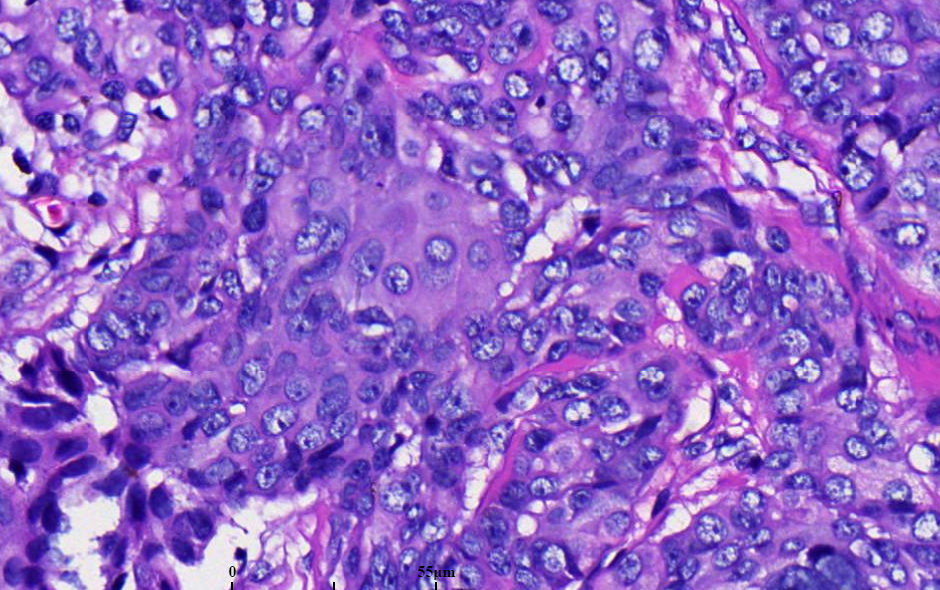

3. 黏液表皮样癌由表皮样细胞、产黏液细胞和中间型细胞构成。

4. 黏液细胞:体积大,胞质苍白,核位于细胞边缘,一般少于肿瘤细胞总数的 10%。

5. 中间型细胞:基底样或立方状,在肿瘤细胞中占多数。

6. 表皮样细胞:呈多边形,角化罕见。

7. 有时可见透明细胞、柱状细胞和/或嗜酸性粒细胞。

8. 不同类型的细胞的比例和所形成的结构在肿瘤内和肿瘤间质均有不同。

9. 坏死、间变、核分裂不同病例差异较大。